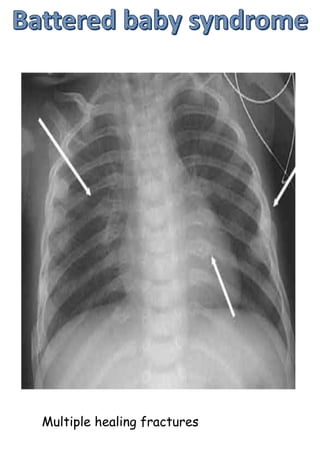

Multiple healing fractures

Female>male

50% cases bilateral